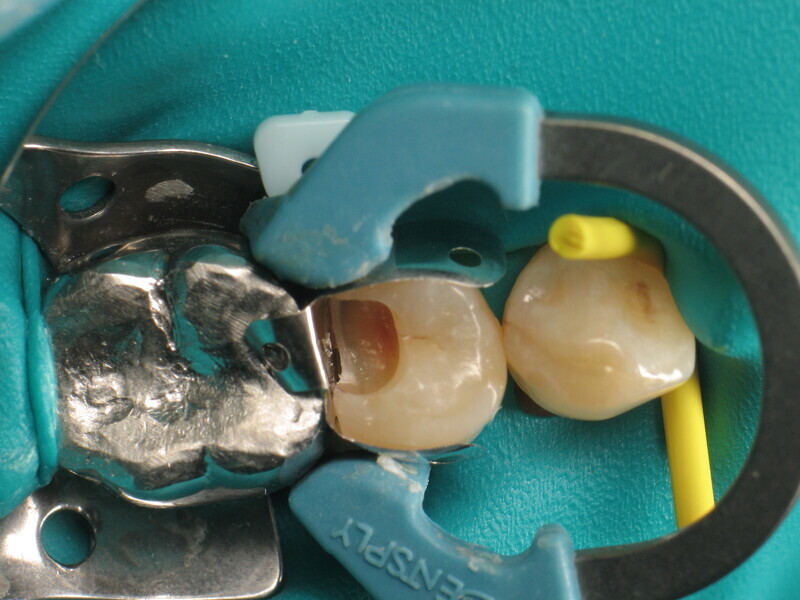

Fig. 1 : Prémolaire avec carie de classe II. (Photos : Yassine Harichane)

Le cas clinique décrit dans cet article porte sur une cavité de classe II sur une prémolaire (45) qui sera restaurée à l’aide d’un composite thermovisqueux (Fig. 1). La dent est isolée avec une digue en latex (Fig. 2). La cavité de classe II est ensuite nettoyée (Fig. 3). Afin d’obtenir une paroi distale anatomiquement correcte, une matrice, un coin et un anneau sont placés (Fig. 4). L’émail dentaire est ensuite mordancé pendant 30 secondes et la dentine pendant 15 secondes (Conditioner 36, Dentsply Sirona ; Fig. 5) puis rincé abondamment (Fig. 6). En raison de la faible épaisseur de dentine restante, une protection pulpaire (Telio Desensitizer, Ivoclar) est également appliquée (Fig. 7). L’adhésif (Futurabond DC, VOCO) est déposé dans la cavité pendant 20 secondes puis séché 5 secondes sous un jet d’air non gras et enfin, photopolymérisé pendant 10 secondes (Figs. 8 et 9). Pour un mouillage optimal, le fond de la cavité est recouvert d’un composite fluide extrêmement fin (GrandioSO Light Flow, A3.5, VOCO) et durci en 20 secondes (Figs. 10 et 11).